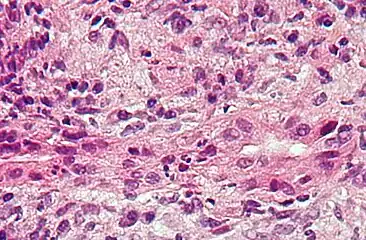

| Micrograph of PBC showing bile duct inflammation and injury, H&E stain | |

Low-magnification micrograph of PBC, H&E stain Intermediate-magnification micrograph of PBC showing bile duct inflammation and periductal granulomas, liver biopsy, H&E stain

On microscopic examination of liver biopsy specimens, PBC is characterized by chronic, nonsuppurative inflammation, which surrounds and destroys interlobular and septal bile ducts. These histopathologic findings in primary biliary cholangitis include:[32]

- Inflammation of the bile ducts, characterized by intraepithelial lymphocytes

- Periductal epithelioid granulomas.

- Proliferation of bile ductules

- Fibrosis (scarring)